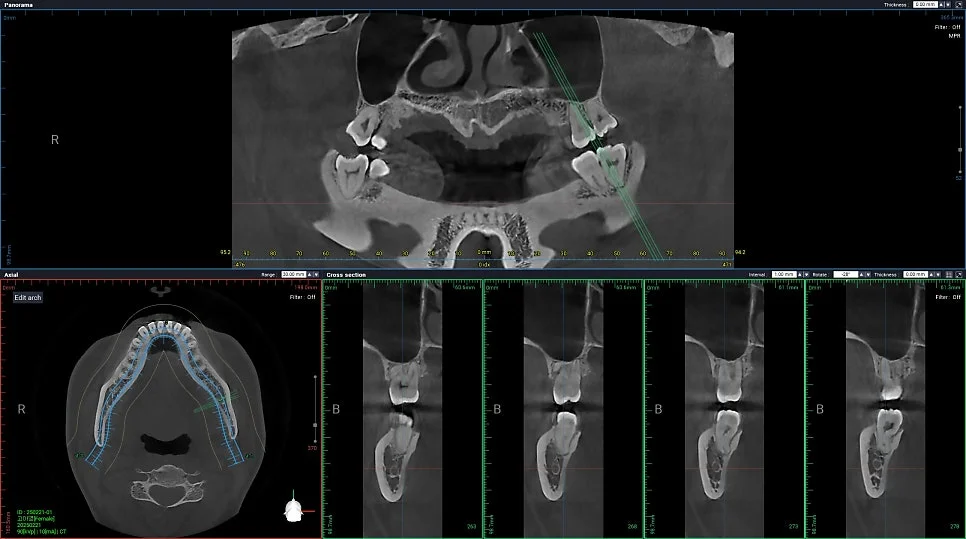

CBCT 진단 — 신경관 위치 사전 확인

CT를 보면 사랑니가 신경관과 꽤나 가까이 맞닿아 있는 상태가 확인되었습니다.

이런 경우에는 CT 검사가 선택이 아니라 필요한 과정인데요. 정확한 영상을 통해 발치 동선을 사전에 계획할 수 있어 신경 손상과 같은 위험 요소를 대폭 줄일 수 있습니다.

사랑니가 신경관에 가까울수록 하치조신경 손상 위험이 있기 때문에 사전 CBCT(3D CT) 검사가 필수입니다. 정확한 영상을 통해 발치 동선을 사전에 계획할 수 있어 신경 손상 위험을 대폭 줄일 수 있습니다. 서울쏙쏙치과에서는 CT를 통해 신경관 위치를 확인한 후 안전한 경로를 설계하여 발치합니다.